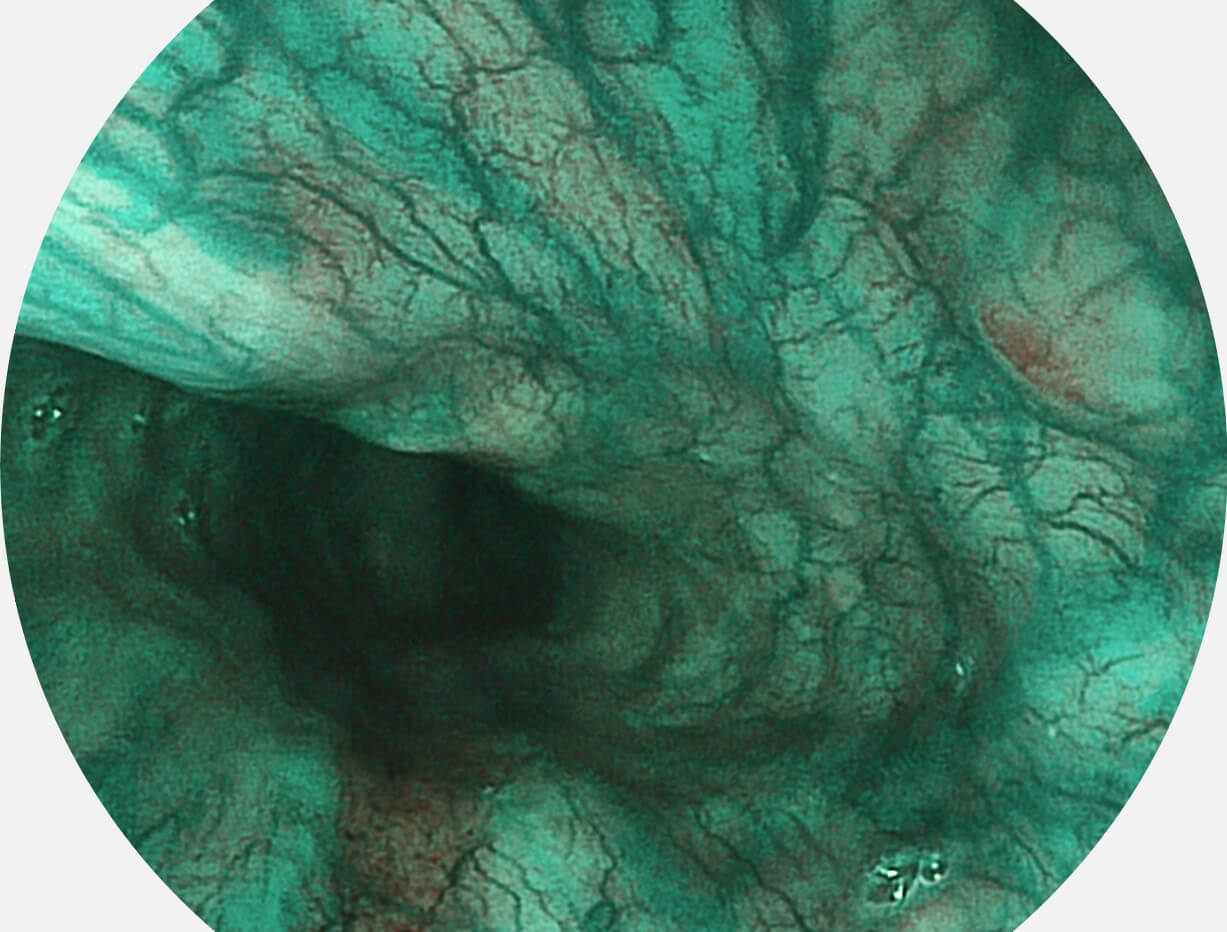

Versatile Intelligent Staining Technology, VIST

强调浅层黏膜结构的同时,保证照明亮度和提升浅层微血管与中层血管颜色对比度,病变边界更清晰。

血管对比度分布光谱曲线

VIST光谱

VIST图像